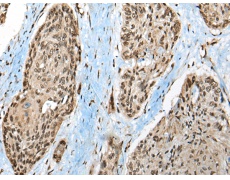

IHC positive control: |

Human esophagus cancer and human ovarian cancer |

IHC Recommend dilution: |

50-300 |